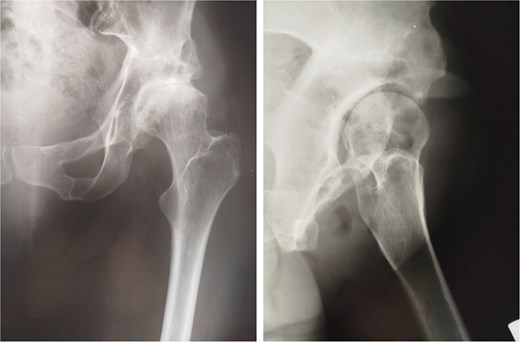

At 20-year follow-up, she presented with symptomatic hip pain. Pelvic radiographs (Fig. 2) showed signs of moderate osteoarthritis in the left hip (Tönnis Grade III). Radiographs showed signs of acetabular retroversion (ischial spine sign and posterior wall sign).

Postoperative radiographs of the pelvis 20 years after pelvic osteotomy, showing signs of moderate osteoarthritis in the left hip (Tönnis Grade III), and radiographic evidence of acetabular retroversion (ischial spine sign and posterior wall sign).